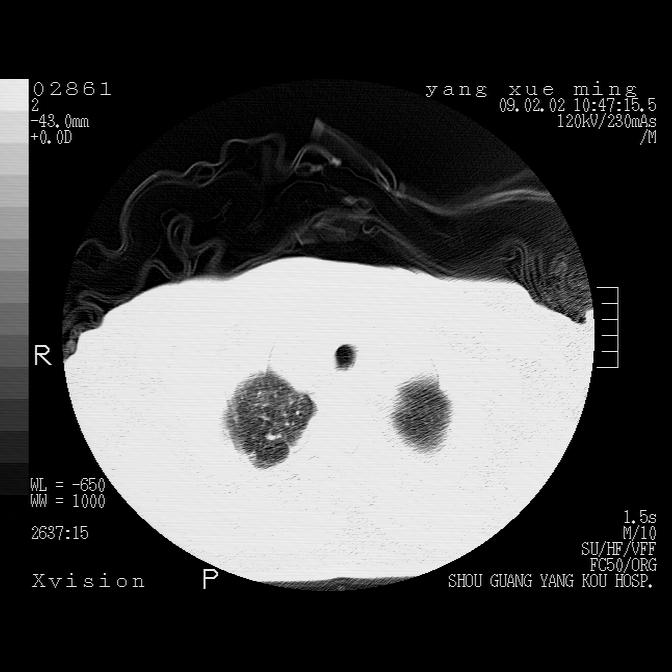

以下是引用lkc8963在2009-2-3 20:11:00的发言:[br]1)右上肺陈旧病灶。2)右下肺团块及团片影,影像表现符合感染。3)左心增大,左冠脉钙化,符合冠心病。4)双侧肺门扩大,以左侧为著,肺动脉干略粗,左上肺局限性气肿,为谨慎起见,需除肿瘤,建议增强。

以下是引用zbp537在2009-2-3 19:08:00的发言:[br]我诊断为肺泡性肺水肿。[br]诊断依据:[br]1、心影普遍增大,肺血管增粗,并见絮状高密度影,肺门改变显著。[br]2、临床上表现胸闷咳嗽,无发烧,不是一个典型的肺部感染的病史。